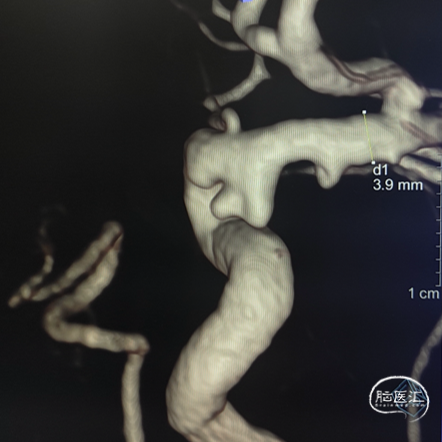

右侧颈内动脉3D造影:右侧颈内动脉C6动脉瘤。

右侧颈内动脉造影重建:右侧颈内动脉动脉瘤。